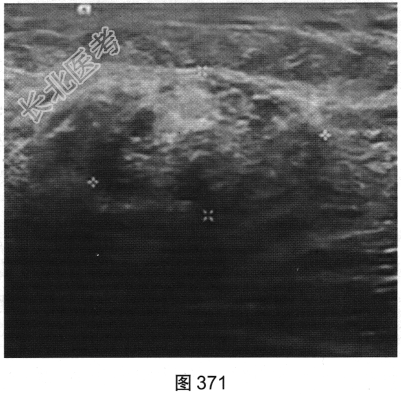

- 多项选择题2.[提示]患者行X线及超声检查,如图369~图372所示。X线及超声的影像学表现是( )

B、超声示左乳皮下脂肪层低回声肿块

D、超声示左乳腺体浅部高回声肿块伴边缘无回声区

E、X线示左乳外上象限不规则肿块伴细小多形性钙化

G、超声示肿块内血流丰富

H、超声示左乳腺体深部低回声肿块